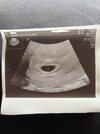

chłopak w ogóle nie mógł ze mna wejść ponieważ „będzie ja to rozpraszało i będzie tysiąc pytań” badanie na fotelu było dosyć nieprzyjemne i niedelikatne ale mniejsza o to. Potem zrobiła usg i stwierdziła ze pęcherzyk co do wielkości jest dobry i ze „cos tam w środku majaczy ale może być za wcześnie” i powiedziała tez ze jest cień echa serca ale to jeszcze może być za wcześnie. Na wizytę 5 lipca poleciła iść żeby zobaczyć już serduszko a do tego czasu mam zrobić podstawowe badania w tym to moje podwyższone tsh. Generalnie mam wrażenie ze starała się być miła ale mega na sile jakby mi łaskę robiła ze do niej przyszłam

gdy już powiedziała ze należy się 200 zł bez zadania przeze mnie żadnego pytania to zdążyłam tylko się dowiedzieć odnośnie tej bety ze jak już pęcherzyk jest to nie ma co się tym kierować tylko miarodajne jest już tylko usg.

Podsumowując więcej już do niej nie pójdę i mam nadzieje ze lekarka 5 lipca okaże się lepsza ale najważniejsze ze potwierdziła ciąże i ze wszystko okej